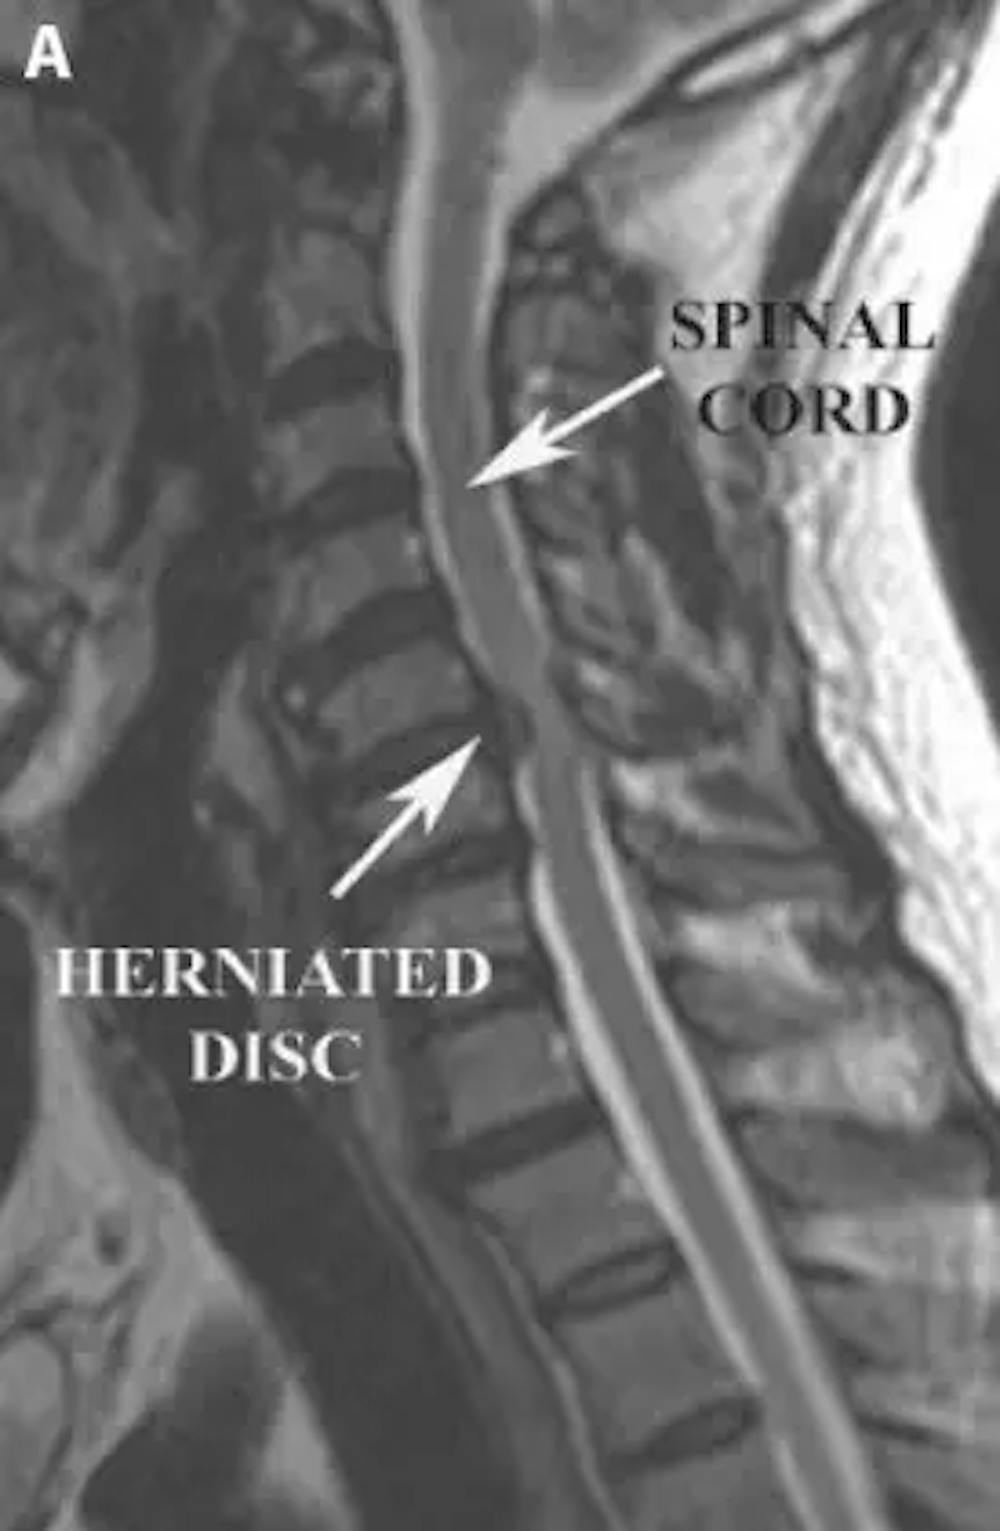

Cuando se sospecha de una hernia discal, las pruebas diagnósticas como la resonancia magnética y/o la tomografía computarizada pueden proporcionar los detalles anatómicos para confirmar el diagnóstico.

A) Resonancia magnética sagital ponderada en T2 preoperatoria que demuestra una hernia discal cervical que comprime la médula espinal

Cuando un disco cervical se hernia, puede llegar a comprimir una raíz nerviosa y a veces incluso la médula espinal. Cuando se comprime una raíz nerviosa, el paciente puede experimentar un dolor de cuello que se irradia al hombro y/o al brazo. Si la compresión de la raíz nerviosa es grave, el paciente puede experimentar debilidad en los grupos musculares asociados.

Cuando una hernia discal comprime la médula espinal puede dar lugar a una constelación diferente de síntomas denominada mielopatía cervical. En el caso de la mielopatía cervical, el paciente suele quejarse de dificultad para utilizar las manos al realizar tareas de motricidad fina (como escribir con un bolígrafo o abotonarse una camisa). Esta torpeza de las manos se asocia a veces con el entumecimiento de las puntas de los dedos. Además, la compresión de la médula espinal cervical puede provocar dificultades para caminar, con tropiezos y caídas frecuentes.